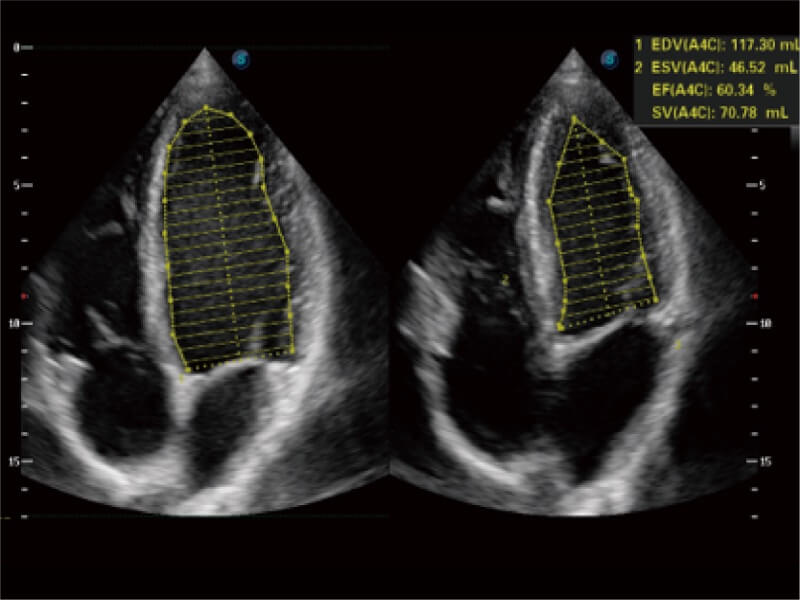

能够基于左心室壁追踪和辛普森法,自动计算射血分数,支持多个可移动点描迹,与手动测量相比,极大节省了动物医生的时间和精力。

能够基于左心室壁追踪和辛普森法,自动计算射血分数,支持多个可移动点描迹,与手动测量相比,极大节省了动物医生的时间和精力。